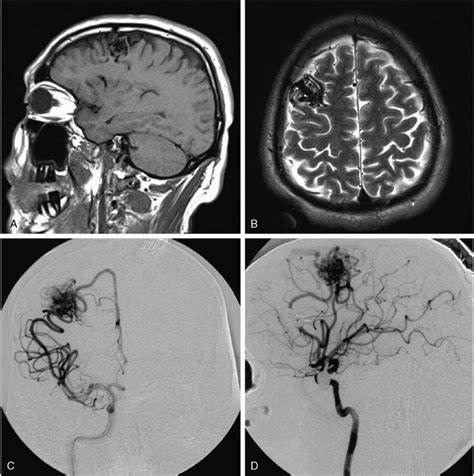

2、后颅窝需手术的血管性疾病,如动脉瘤、动静脉畸形等。